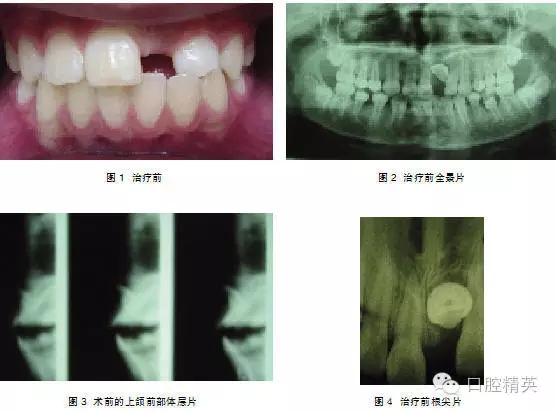

典型病例1: 患者,男,10歲,因左上前門牙未萌出于2009年10月來上海第九人民醫(yī)院預(yù)防、兒童口腔科就診。檢查: |1未萌,1| 全萌,1|2之間間隙為4mm。牙片及全景片示: |1骨內(nèi)埋伏,1| 2之間有埋伏多生牙,多生牙與 |1的重疊,不能清晰顯示多生牙和 |1在頜骨中的具體方位及相關(guān)關(guān)系(圖1-2),采用CBCT掃描后,圖像能清晰顯示多生牙和 |1的形態(tài)、大小、數(shù)目、牙根發(fā)育情況、在頜骨中具體位置、萌出方向及相互關(guān)系(圖3-4),經(jīng)手術(shù)證實(shí)情況與CBCT圖像顯示完全一致,手術(shù)拔除多生牙, |1作外科開窗術(shù)+正畸牽引治療。